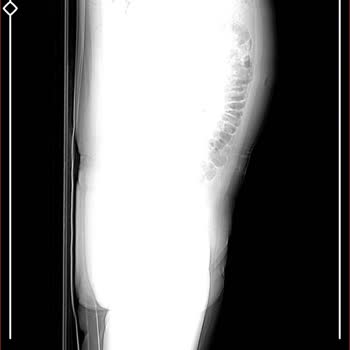

18 Ocak 2026 sabah saat 07.00 civarında Taksim’deki The Elysium Hotel’de 2203 numaralı standart odanın banyosunda çok ciddi bir kaza geçirdim. Banyodaki fayanslar son derece kaygandı, zeminde kaymayı önleyici hiçbir malzeme yoktu ve tutunabileceğim herhangi bir aparat da bulunmuyordu. Duş sırasında ...